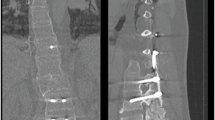

Fifty included papers described 201 individuals with SCI who developed Charcot spine. 86% of individuals had paraplegia and 93% of individuals had a neurologically complete injury. Mean length of initial spinal fusion spanned 7.7 vertebral bodies (SD = 3.9). The most common presenting symptoms were back pain (56%), spinal deformity (48%), and crepitus (34%). Vertebral body destruction (83%), osteophytes (61%), and endplate destruction (57%) were commonly reported on radiographs. Reoccurrence of Charcot spine was described in 19% of cases after initial treatment.

Charcot spine after SCI commonly presents with low back pain and radiologic evidence of vertebral body destruction. Cases have been described more often in individuals with paraplegia and neurologically complete injuries. Surgical management is often pursued. A high rate of reoccurrence of Charcot spine in individuals with SCI after initial treatment has been reported.